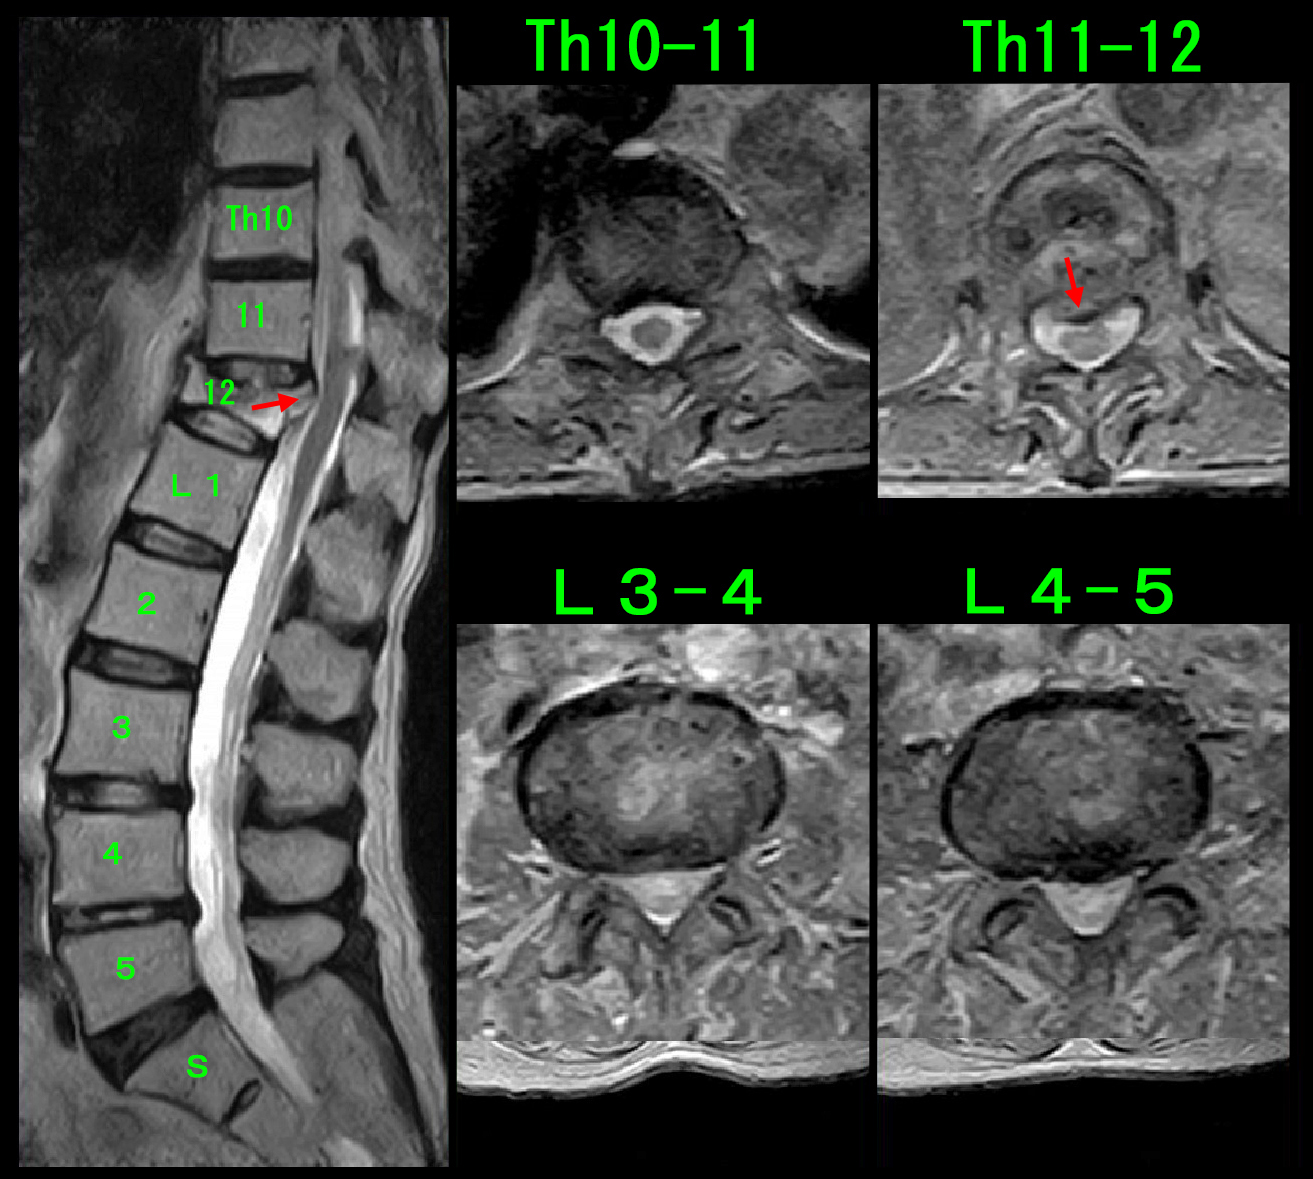

MRI検査ではL4-5高位での中等度の脊髄の圧迫と、Th9-10高位での右優位の中等度の脊髄圧迫が確認され、ずっと続いている背部痛の鈍痛はTh9-10の脊髄圧迫に起因していると診断しました。

背部の鈍痛はVAS4程度のものでしたが、1年9か月も私に訴え続けている症状です。神経根ブロックで軽減するかもしれないと説明すると、ブロック受けるという意向となられました。

令和6年10月15日に実施した、Th10神経根ブロックの画像です。

10月24日にはVAS4の背部痛はVAS0となったと報告していただきました。